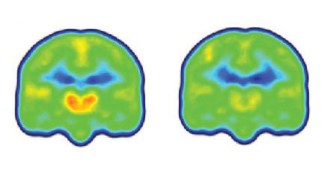

12. Neuroscience

A brain at rest offers clues to Parkinson’s, Alzheimer’s

PET scans reveal that the breakdown of brain networks differs in Parkinson’s and Alzheimer’s diseases.